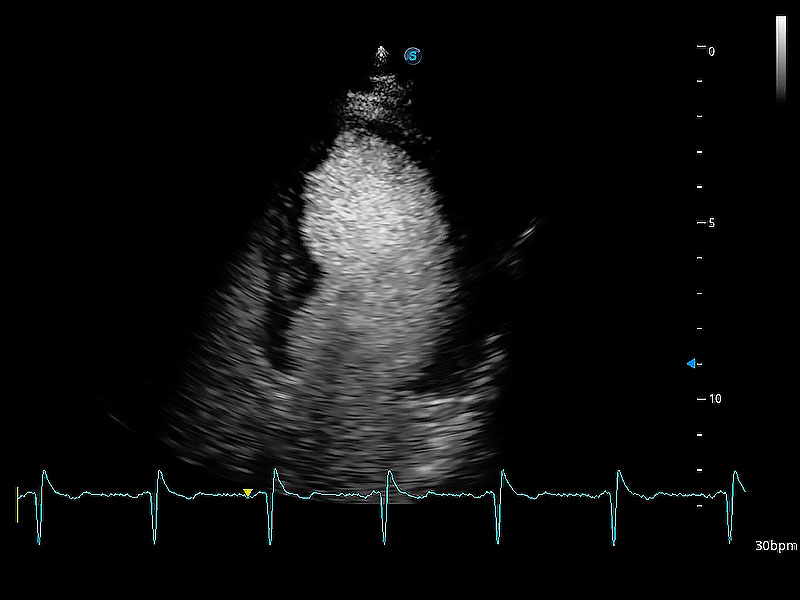

ProPet 80 配備了豐富的心臟探頭群、先進(jìn)的成像技術(shù)和專業(yè)的心臟測量工具,可幫助動物醫(yī)生為不同體型和生理結(jié)構(gòu)的動物提供心臟和心肌功能的全面評估。

通過360度任意調(diào)節(jié)3條M型取樣線,在同一心動周期上觀察心臟不同位置的運(yùn)動曲線,得到準(zhǔn)確的心功能測量數(shù)據(jù),有效評估心肌運(yùn)動及左心室功能。